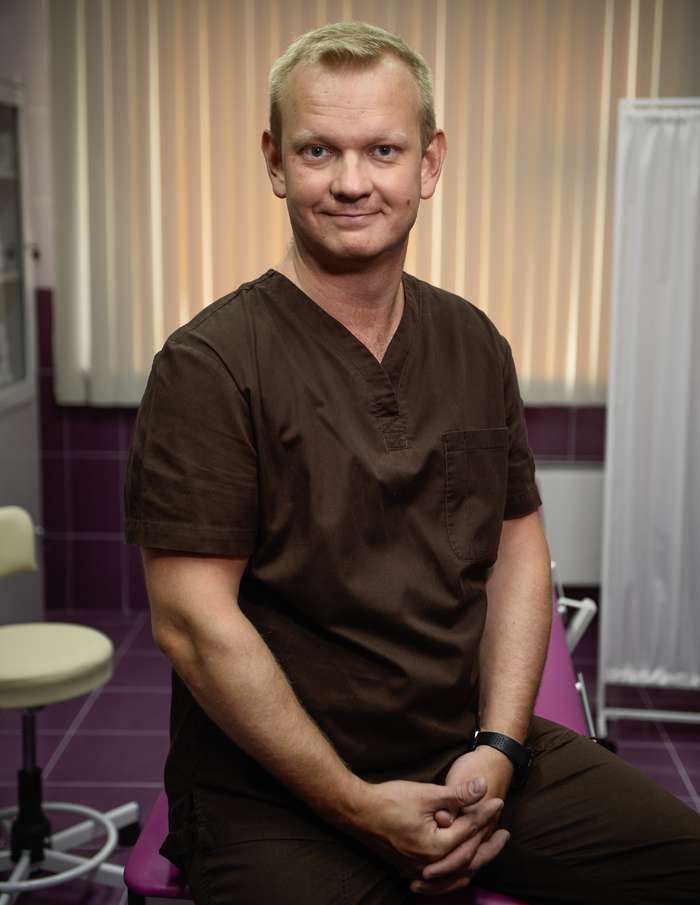

Зимой травматизм резко увеличивается. Это знает любой ортопед-травматолог, вынужденный даже во внеурочное время принимать пациентов в травмпункте. Чем холоднее на улице, чем больше снега и льда — тем длиннее очереди к врачу. Если же наступает гололед, обилие травм приобретает характер эпидемии. Травматолог-ортопед, доктор, кандидат медицинских наук, ведущий специалист в области спортивной травматологии и лечения суставов Юрий Глазков рассказал WomanHit.ru, как себя вести, чтобы в зимнее время не покалечиться.